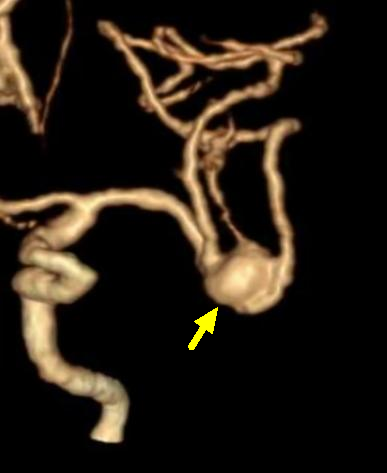

近日,面对一位古稀老人颅内破裂的“不定时炸弹”——复杂脑动脉瘤,我院神经外科团队成功应用全球前沿的自膨式动脉瘤瘤内栓塞器(WEB) ,完成了我院首例该技术下的动脉瘤精准介入治疗。 紧急救治 古稀老人突发“颅内炸弹” 71岁的张先生(化名)突发剧烈头痛伴右侧肢体乏力,经120紧急送入我院。急诊迅速启动卒中绿色通道,经头部CT及CTA检查,诊断为“广泛蛛网膜下腔出血、左侧大脑中动脉分叉部动脉瘤”。此类动脉瘤破裂风险极高,如同颅内的“不定时炸弹”,治疗刻不容缓。 术前颅脑CT见广泛蛛网膜下腔出血 CTA见左侧大脑中动脉分叉部宽颈动脉瘤 创新破局 全球新技解难题 神经外科介入团队立即组织多学科讨论,详细研判病情,制定了开颅夹闭与微创介入栓塞两套方案,家属明确选择微创手术方案。面对位于复杂分叉处且瘤颈宽大的动脉瘤,团队决定应用全球前沿的自膨式动脉瘤瘤内栓塞系统(WEB)进行治疗。在神经外科、介入中心与麻醉科的通力协作下,成功将自膨式动脉瘤瘤内栓塞系统(WEB)装置植入动脉瘤腔内,完成栓塞治疗,历经2小时。术后,造影显示动脉瘤完全隔绝,载瘤动脉通畅良好,危机解除。 技术优势 瘤内扰流新选择 自膨式动脉瘤瘤内栓塞系统(WEB)装置形似精密编织的迷你网篮,专为分叉部宽颈动脉瘤设计。相较于传统支架辅助栓塞,自膨式动脉瘤瘤内栓塞系统(WEB)技术体现了神经介入领域的重要创新: 操作简化: 单一器械即可完成治疗,流程更简洁。 安全性提升: 避免支架植入,降低了血栓等并发症风险。 患者受益: 术后无需长期服用抗血小板药物,减轻了身心及经济负担。 此例自膨式动脉瘤瘤内栓塞系统(WEB)植入术的成功开展,标志着我院在复杂脑动脉瘤微创治疗领域取得新突破,为患者提供了高效的治疗选择。作为国家卫健委能力建设和继续教育神经外科建设中心,贵州航天医院神经外科将持续依托优质资源,深化对外协作,以技术创新护航百姓健康。 神经外科专家简介 廖洪民 神经外科党支部书记、主任,主任医师 临床擅长:从事神经外科临床工作30年,对颅脑损伤、脑肿瘤、脑血管病等具有丰富诊疗经验,擅长救治重症颅脑创伤、脑出血微创治疗、脑肿瘤显微手术治疗、脑立体定向手术等。 中国医师协会神经外科分会专科认证医师、贵州省医学会神经外科分会青年委员、遵义市医学会神经外科分会常务委员、遵义市中西医结合学会脑心同治专业委员会常务委员、中国生命关怀协会脑卒中救治及康复照护专业委员会委员、贵州省脑损伤评价质控中心专家库成员、遵义市脑损伤评价医疗质量控制中心专家。 朱家伟 神经外科副主任医师 临床擅长:从事神经外科工作26年,擅长颅脑损伤救治及脑出血微创手术。 遵义市医学会神经外科分会委员、遵义市中西医结合学会脑心同治专业委员会常务委员。 黄建军 神经外科副主任医师 临床擅长:从事神经外科工作20年,对神经外科常见病、急危重症有丰富诊疗经验,熟练掌握神经外科微创手术。 神经外科科室简介 基本情况 贵州航天医院神经外科于2008年独立建科,是首批国家卫健委能力建设和继续教育神经外科建设中心,贵州省神经外科介入联盟单位。现有专业技术人员17人,其中高级职称4人,中级5人,初级7人。 科室配备STORZ神经内镜系统、德国莱卡手术显微镜,国产西山开颅动力系统、蛇牌双极电凝、Mayfield头架等颅脑手术设备,以及无创和有创颅内压监护仪、正中神经刺激仪、脑循环康复治疗仪、排痰机、下肢康复训练器、气垫床、多参数监护仪等现代化医疗设备,为病区各种急、危、重患者的观察、监护和治疗保驾护航。 专科特色 (一)脑出血微创手术治疗 应用范围:各种病因导致的自发性脑出血(高血压脑出血、脑淀粉样血管病相关脑出血、抗凝药物相关脑出血等)。 技术优势:微创、精准、恢复快。 (二)颅脑病变显微切除术 应用范围:颅内各种占位性病变(脑囊肿、脑肿瘤等)。 技术优势:精确度高、创伤小、恢复快。 (三)颅脑创伤综合救治 应用范围:各种类型的颅脑损伤、创伤性颅内血肿及颅脑创伤并发症、后遗症等。 技术优势:快速精准诊断、个体化手术与监护、早期康复干预,伤者病死率低、并发症少。